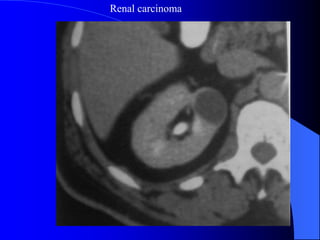

CLVT thì bài tiết

Renal carcinoma

4.1. U nhumä tháûn - Carcinome tãú baìo tháûn Ung thæ tháûn chiãúm 3% ung thæ caïc loaûi åí ngæåìi låïn, 95% trãn 50 tuäøi, nam gáúp âäi næî. Yãúu täú thuáûn låüi laì tháûn âa nang, suy tháûn kãút håüp âa nang màõc phaíi, tháûn dë daûng hçnh moïng ngæûa, nghiãûn thuäúc laï. Caïc loaûi u aïc tênh khaïc åí tháûn nhæ di càn, lymphome, caïc loaûi sarcome, u nguyãn baìo tháûn åí ngæåìi låïn.

- CLVT phánbiãût khäúi âàûc hay dëch, phaït hiãûn väi hoïa nhoí, xuáút huyãút trong u, tçnh traûng tæåïi maïu cuía u. Pháön låïn træåìng håüp phán biãût âæåüc u laình vaì u aïc. Xem xeït âæåìng dáùn niãûu bë giaîn, bë xám láún. CLVT kiãøm tra di càn haûch xám láún vuìng xung quanh, xám láún maûch maïu, di càn xa, cå såí âãø phán giai âoaûn tiãún triãøn u, cáön thiãút cho phæång phaïp âiãöu trë.